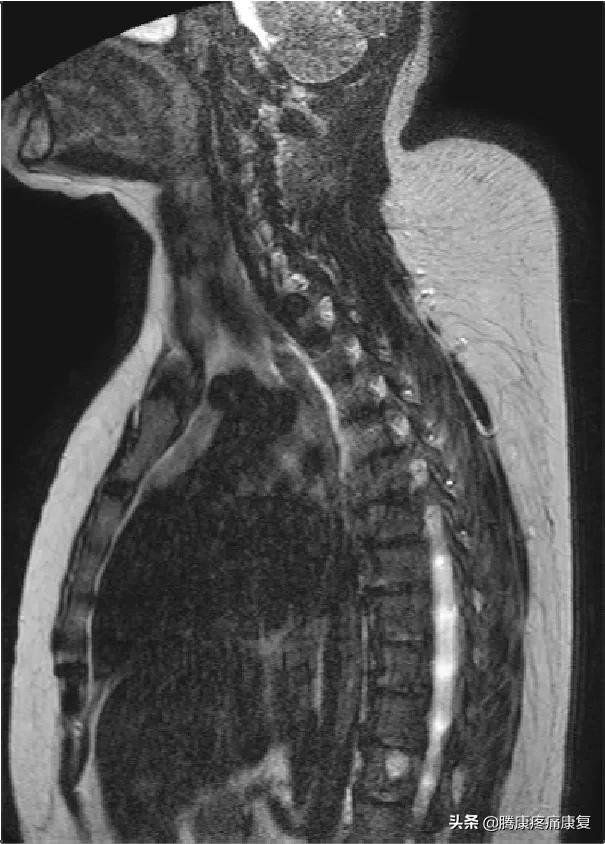

颈后大包,我们怎么才能甩掉它

你可能注意到了,脖子后面凸起了一块像驼峰一样的肿块,你可能想知道这是什么,有害么?我能摆脱这个肿块么?实际上这些凸起是在肩颈相交的地方堆积起来的一块脂肪,通常被称为水牛肩或是富贵包。

水牛背本身不会引起严重的副作用,不严重的话一般通过理疗和自我家庭训练就可以纠正,一旦摆脱了水牛背,还可以通过自我锻炼来防止它再次发生。但是如果水牛背持续存在,可能是还请立即就诊,这有可能是由于其他原因导致的。

水牛背是怎么形成的

水牛背的成因有很多种,导致这种情况的原因,是由于现代的工作方式长期久坐导致的脊柱弯曲。但是更主要的是由于血液中过度产生糖皮质激素、皮质醇或肩部脂肪堆积过多导致。

激素失衡可能由于高剂量的某些药物,如类固醇,或内分泌失调例如库欣综合征。库欣综合征可由于体内异常引起,例如肾上腺肿瘤导致的肾上腺分泌过多的皮质类固醇激素,水牛肩也可以因肥胖导致的骨质疏松症而恶化。

同时水牛背也可能伴随有骨质疏松症的相关症状,包括脊柱后凸或脊柱侧弯等症状。

水牛背的形成会造成肩胛部位酸痛和不灵活,有时还会压迫神经到时手部麻木无力,甚至还会导致中枢神经紊乱。

肩胛部位位于心肺后侧,肩胛处失去弹性久而久之也会对心肺功能产生影响。